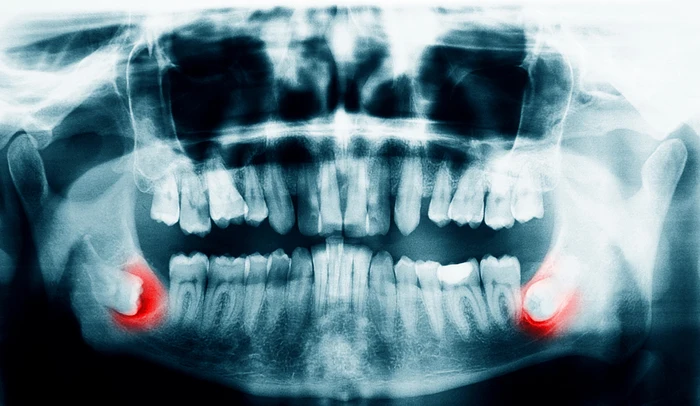

- lõualuus peetunud tarkusehamba eemaldamine

Tarkusehamba väljatõmbamine on levinud protseduur, mida tehakse juhul, kui hammas ei mahu korralikult suhu, põhjustab valu, põletikku või mõjutab teisi hambaid.

Protseduur viiakse läbi kohaliku tuimestusega ning vajadusel tehakse sisselõige igemesse, et hammas ohutult eemaldada.

Meie spetsialist hindab sinu hammaste tervist, teeb vajadusel röntgenuuringu ning selgitab protseduuri kulgu ja taastumiseks vajalikke samme.